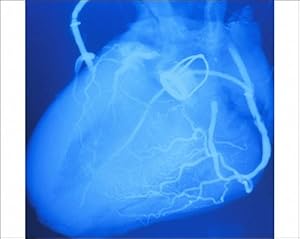

Product Description : Size: 10 x8 Print10 x8 Print showing Artificial heart valve. False-colour angiogram (X-ray image) of the human heart, showing a mechanical Starr-Edwards aortic heart valve. A normal aortic valve regulates the flow of blood from the left ventricle into the aorta, the body s main artery, for distribution around the circulation. The valve consists of three cusps, shaped like half-moons. Malfunctions of the valve include fusion of the cusps, often the result